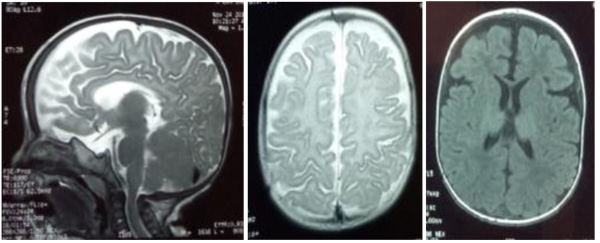

The patient, a 7-month-old male infant, the only living son of parents of a second degree consanguineous marriage, was born at full-term and adapted well to extrauterine life. His psychomotor development was normal until the age of 4 months (gesticulated normally, smiled, followed light). An older brother had died at the age of 6 months due to respiratory distress with a clinical picture of psychomotor retardation, macrocephaly, abdominal distension, and blue-grey pigmented cutaneous spots. The present patient was hospitalized (1st hospitalization) for respiratory distress with the appearance of cutaneous spots and psychomotor regression since the age of 4 months. He had coarse facial features, macrocephaly (cranial circumference + 3DS), abolished tendon reflexes, significant psychomotor retardation (axial hypotonia, no voluntary prehension, no smile, sitting position even with unearned support), slate-grey spots scattered on the trunk and limbs, a negative Darier sign, and some atrophic lesions on the trunk (Fig. 1). The ophthalmological examination suggested bilateral blindness (did not follow light), a pale papilla, but no cherry-red macular spot. He had no skeletal deformities. Brain imaging showed matter myelination abnormalities, enlargement of frontotemporal subarachnoid space and hypoplasia of the corpus callosum (Fig. 2). Abdominal ultrasonography revealed homogeneous hepatosplenomegaly. He had no atypical or vacuolated lymphocytes on the blood smear, liver and thyroid tests were normal, the amino acid chromatography was normal and the urinary excretion of glycosaminoglycans was negative. The presence of oligosaccharides in the urine, and serum beta-galactosidase deficiency confirmed the diagnosis of GM1-gangliosidosis. The progression was marked by death at the age of 9 months after severe neurological deterioration. The infant died before genetic testing could be performed and genetic counselling was planned for the parents.

Fig. (2). MRI scans showing matter myelination abnormalities, enlargement of the fronto-temporal subarachnoid space, and hypoplasia of the corpus callosum. |